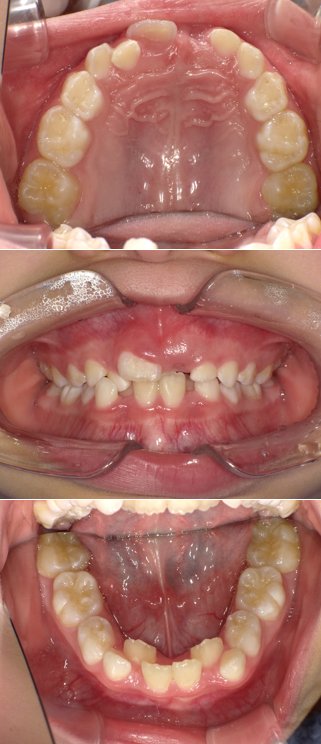

AFTER

年齢:9歳 女の子

主訴/治療内容:

お子様の歯並びが気になり、他院様でプレオルソの治療を開始したが、改善する見込みがなくご相談に来られました。現在まだ経過観察途中ですが、当院でプレオルソ治療を開始して9ヵ月でこれだけ歯並びが改善されました。装置は寝ている間に装着するだけです。早期に治療を開始することで、将来的な矯正を未然に防ぎ、経済的負担・治療の負担を大幅に軽減することが可能になります。同様のケースで少しでも気になっていらっしゃいましたら、是非お気軽にご相談ください。

治療期間/通院回数:プレオルソ装着9ヵ月 経過観察途中

費用: 精密検査・診断料 71,500円  0期治療 55,000円